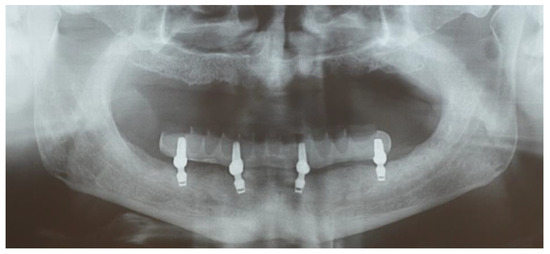

Edentulous Mandibles Restored with Fiber-Reinforced Composite Prostheses Supported by 5.0 mm Ultra-Short Implants: Ten-Year Follow-Up

2. Materials and Methods

3. Results

| MBL (mm) | Baseline | 0.18 (0.1–0.3, 0.08) | <0.001 | 0.12 (0.09; 0.15) | <0.001 | BL vs. 5 y |

| 5 years | 0.05 (−0.2–0.25, 0.1) | 0.09 (0.03; 0.15) | 0.02 | 5 y vs. 10 y | ||

| 10 years | −0.03 (−0.4–0.4, 0.21) | 0.21 (0.16; 0.27) | <0.001 | BL vs. 10 y | ||